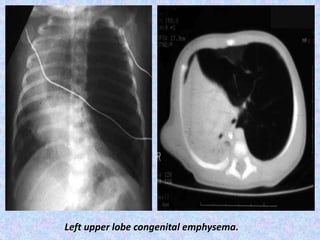

Left upper lobe congenital emphysema.

Congenital Lobar Emphysema. CLEalmost always involves one lobe, with rates of occurrence as follows: Left upper lobe - 41% Right middle lobe - 34% Right upper lobe - 21% Congenital lobar emphysema has 2 forms: Hypoalveolar (fewer than expected number of alveoli) Polyalveolar (greater than expected number of alveoli) X-Ray shows unilateral –translucency. CT Scan shows hyperinflation of one or more lobes with attenuated pulmonary vasculatures, compression atelectasis of the adjacent lung and mediastinal shift.

Left upper lobecongenital emphysema.